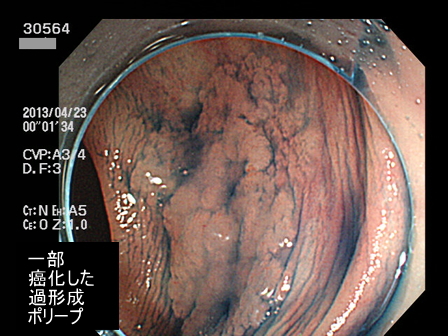

上記100名より抽出した平坦・陥凹型腺腫(=癌化の危険が高いが見落としやすい病変)の内視鏡写真

30500 30502 30504 30506 30510 30512 30513 30519 30520 30521 30523 30524 30526 30529 30530 30532 30533 30534 30535 30540 30543 30545 30546 30548 30551 30552 30554 30555 30558 30560 30561 30562 30564 30565 30568 30571 30572 30573 30574 30575 30576 30583 30584 30585 30586 30587 30588 30591 30592 30593 30596 30597・・・・・・の52名